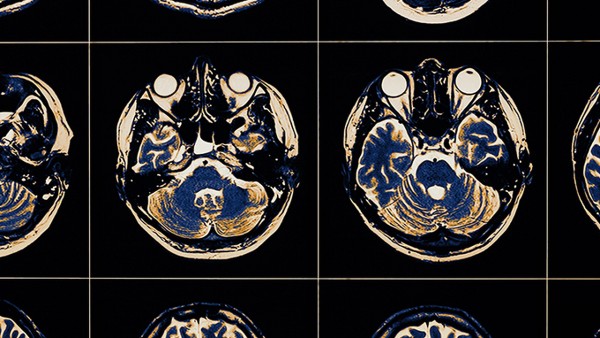

臨床前藥理試驗(yàn)表明,腦血栓片可減輕局部腦缺血大鼠腦壞死的重量,提高全腦缺血小鼠的抗缺氧能力,減少腦組織MDA的產(chǎn)生,減緩能量代謝,增加正常腦膜血流量,保護(hù)缺血心肌,延長缺氧存活時(shí)間,抑制體外血栓形成,具有抗凝作用。

現(xiàn)代中藥在治療腦梗死等慢性病方面具有長效性強(qiáng)、安全性高、耐藥性差等優(yōu)點(diǎn),但缺點(diǎn)是有效成分含量不穩(wěn)定,劑量大。腦血栓片的主要功能是促進(jìn)血液循環(huán),消除血瘀,清醒大腦,通絡(luò),潛陽,熄風(fēng)。用于血瘀、肝陽上亢等中風(fēng)先兆,如肢體麻木、頭暈、腦血栓形成中風(fēng)、口眼歪斜。偏癱等疾病。具有預(yù)防和治療效果。